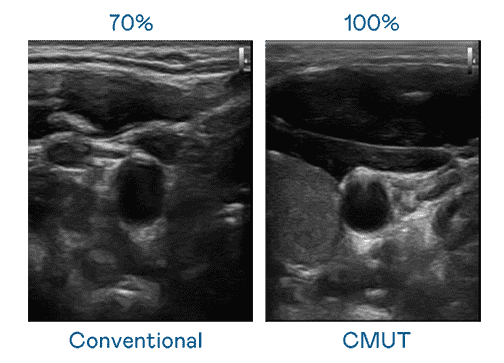

CMUT 技术是一种用电容式微机电元件来产生超音波讯号的技术。。。与传统 PZT 压电式技术相比,,,CMUT 频宽增加 30%,,,,更宽频的超音波讯号让影像解析度大幅提升,,,是实现高影像品质医疗超音波扫描、、促进精准医疗发展的关键技术。。。

超音波影像的解析度高低,,,,首先取决于探头能发出的讯号频宽。。杏悦2 CMUT 可提供高清晰的超音波讯号,,提供高频宽、、高灵敏度、、、影像纹理细节更高的超音波影像,,协助医护人员缩短影像判读时间及利用精准的医疗影像进行诊断。。。